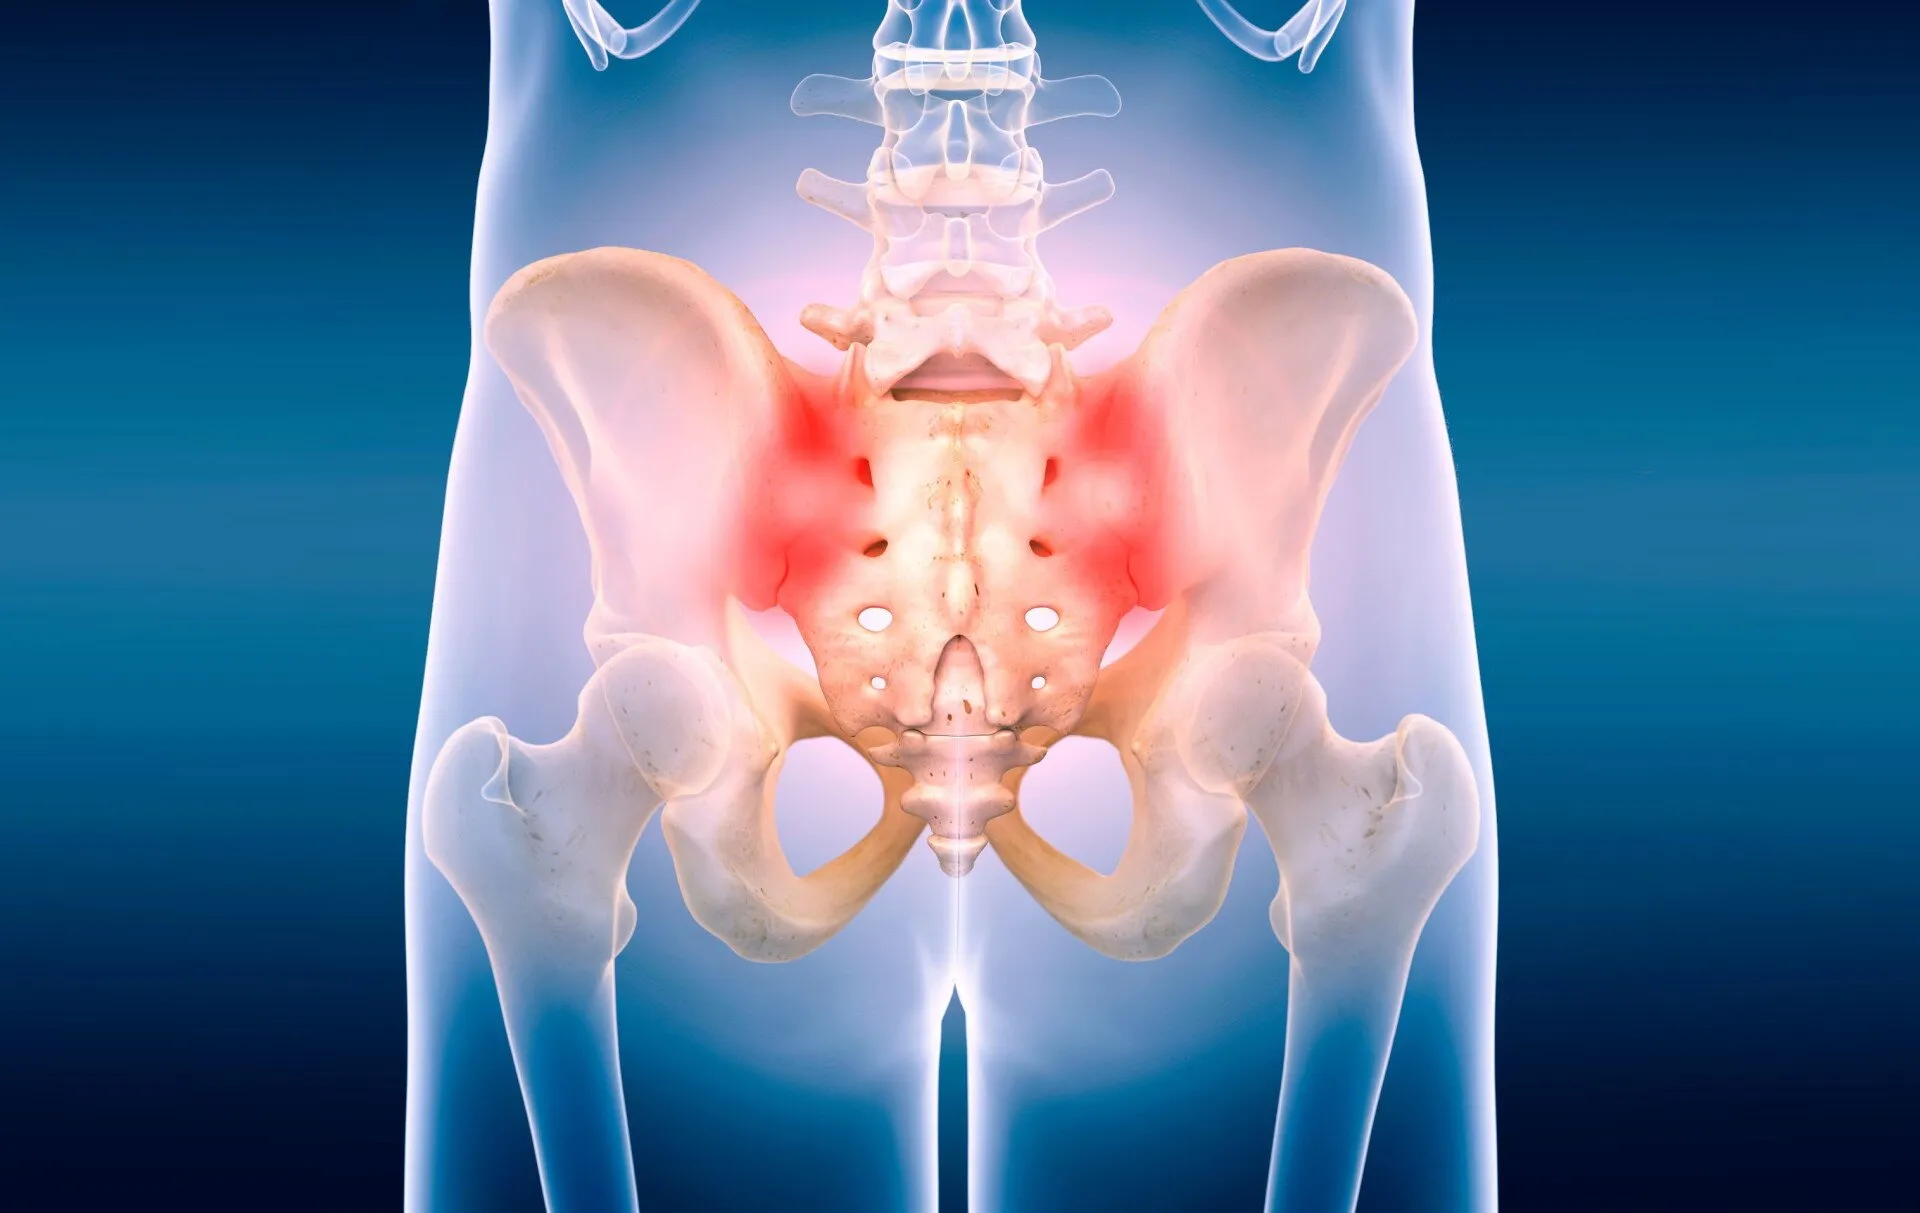

ساکروایلیت به التهاب مفصل ساکروایلیاک گفته میشود که بین استخوان ساکروم (انتهای ستون فقرات) و استخوانهای لگن قرار دارد. این مفصل نقش مهمی در انتقال وزن از ستون فقرات به پاها دارد و هرگونه التهاب در آن میتواند منجر به درد و محدودیت حرکتی شود.

بیماران مبتلا معمولاً درد را در ناحیه باسن، لگن یا پایین کمر احساس میکنند. این درد ممکن است به رانها یا حتی پاها انتشار یابد و با فعالیتهایی مانند ایستادن طولانی یا بالا رفتن از پلهها بدتر شود. تشخیص به موقع و درمان مناسب، مانع از مزمن شدن این بیماری خواهد شد.

مهمترین علامت ساکروایلیت درد در ناحیه لگن و پایین کمر است. این درد اغلب با نشستن طولانی یا تغییر وضعیت ناگهانی افزایش مییابد. بیماران ممکن است سفتی و خشکی مفصل را نیز تجربه کنند.

ناحیه لگن و مفصل ساکروایلیاک

✅ فیزیوتراپی لگن → اصلیترین بخش درمان چون مفصل ساکروایلیاک در لگن قرار دارد.